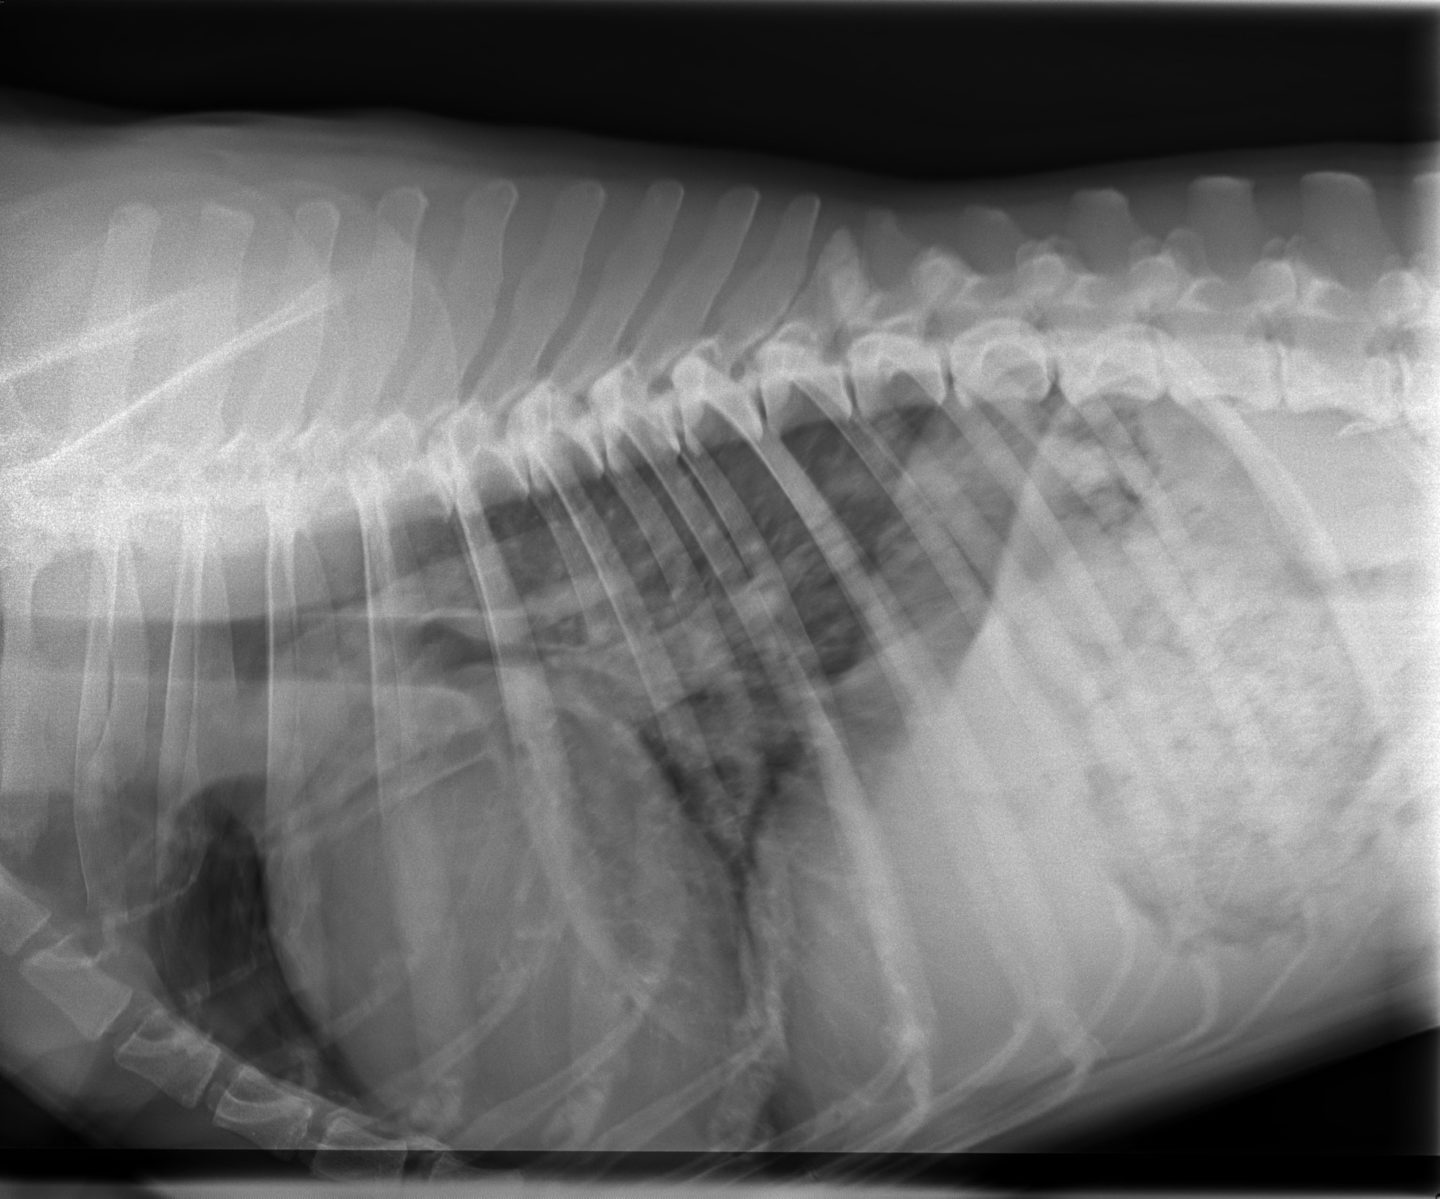

Außerdem habe ich eine Röntgenaufnahme von Momos Brustkorb angefertigt. Diese zeigte dann auch eine Verschattung der hinteren Lungenlappen. Die Herzsilhouette war vergrößert und es war eine Stauung der Lungenvenen zu erkennen, was auf ein kardial bedingtes Lungenödem schließen lässt. Es befand sich also Wasser in Momos Lunge.

Ein Röntgenbild kann jedoch höchstens Hinweise auf Herzerkrankungen geben – allein genügt es nicht für eine sichere Diagnose. Ich habe daher das Herz noch einmal genauer mittels Ultraschall untersucht. Diese sogenannte Echokardiographie zeigte bei Momo eine deutlich vergrößerte linke Herzkammer mit sehr dünnen Herzwänden und einer stark verminderten Kontraktilität (die Herzkammer zieht sich also deutlich weniger stark zusammen als normalerweise). Daneben war auch der linke Vorhof vergrößert. Ich musste daher als Diagnose eine Dilatative Kardiomyopathie (DCM) feststellen.